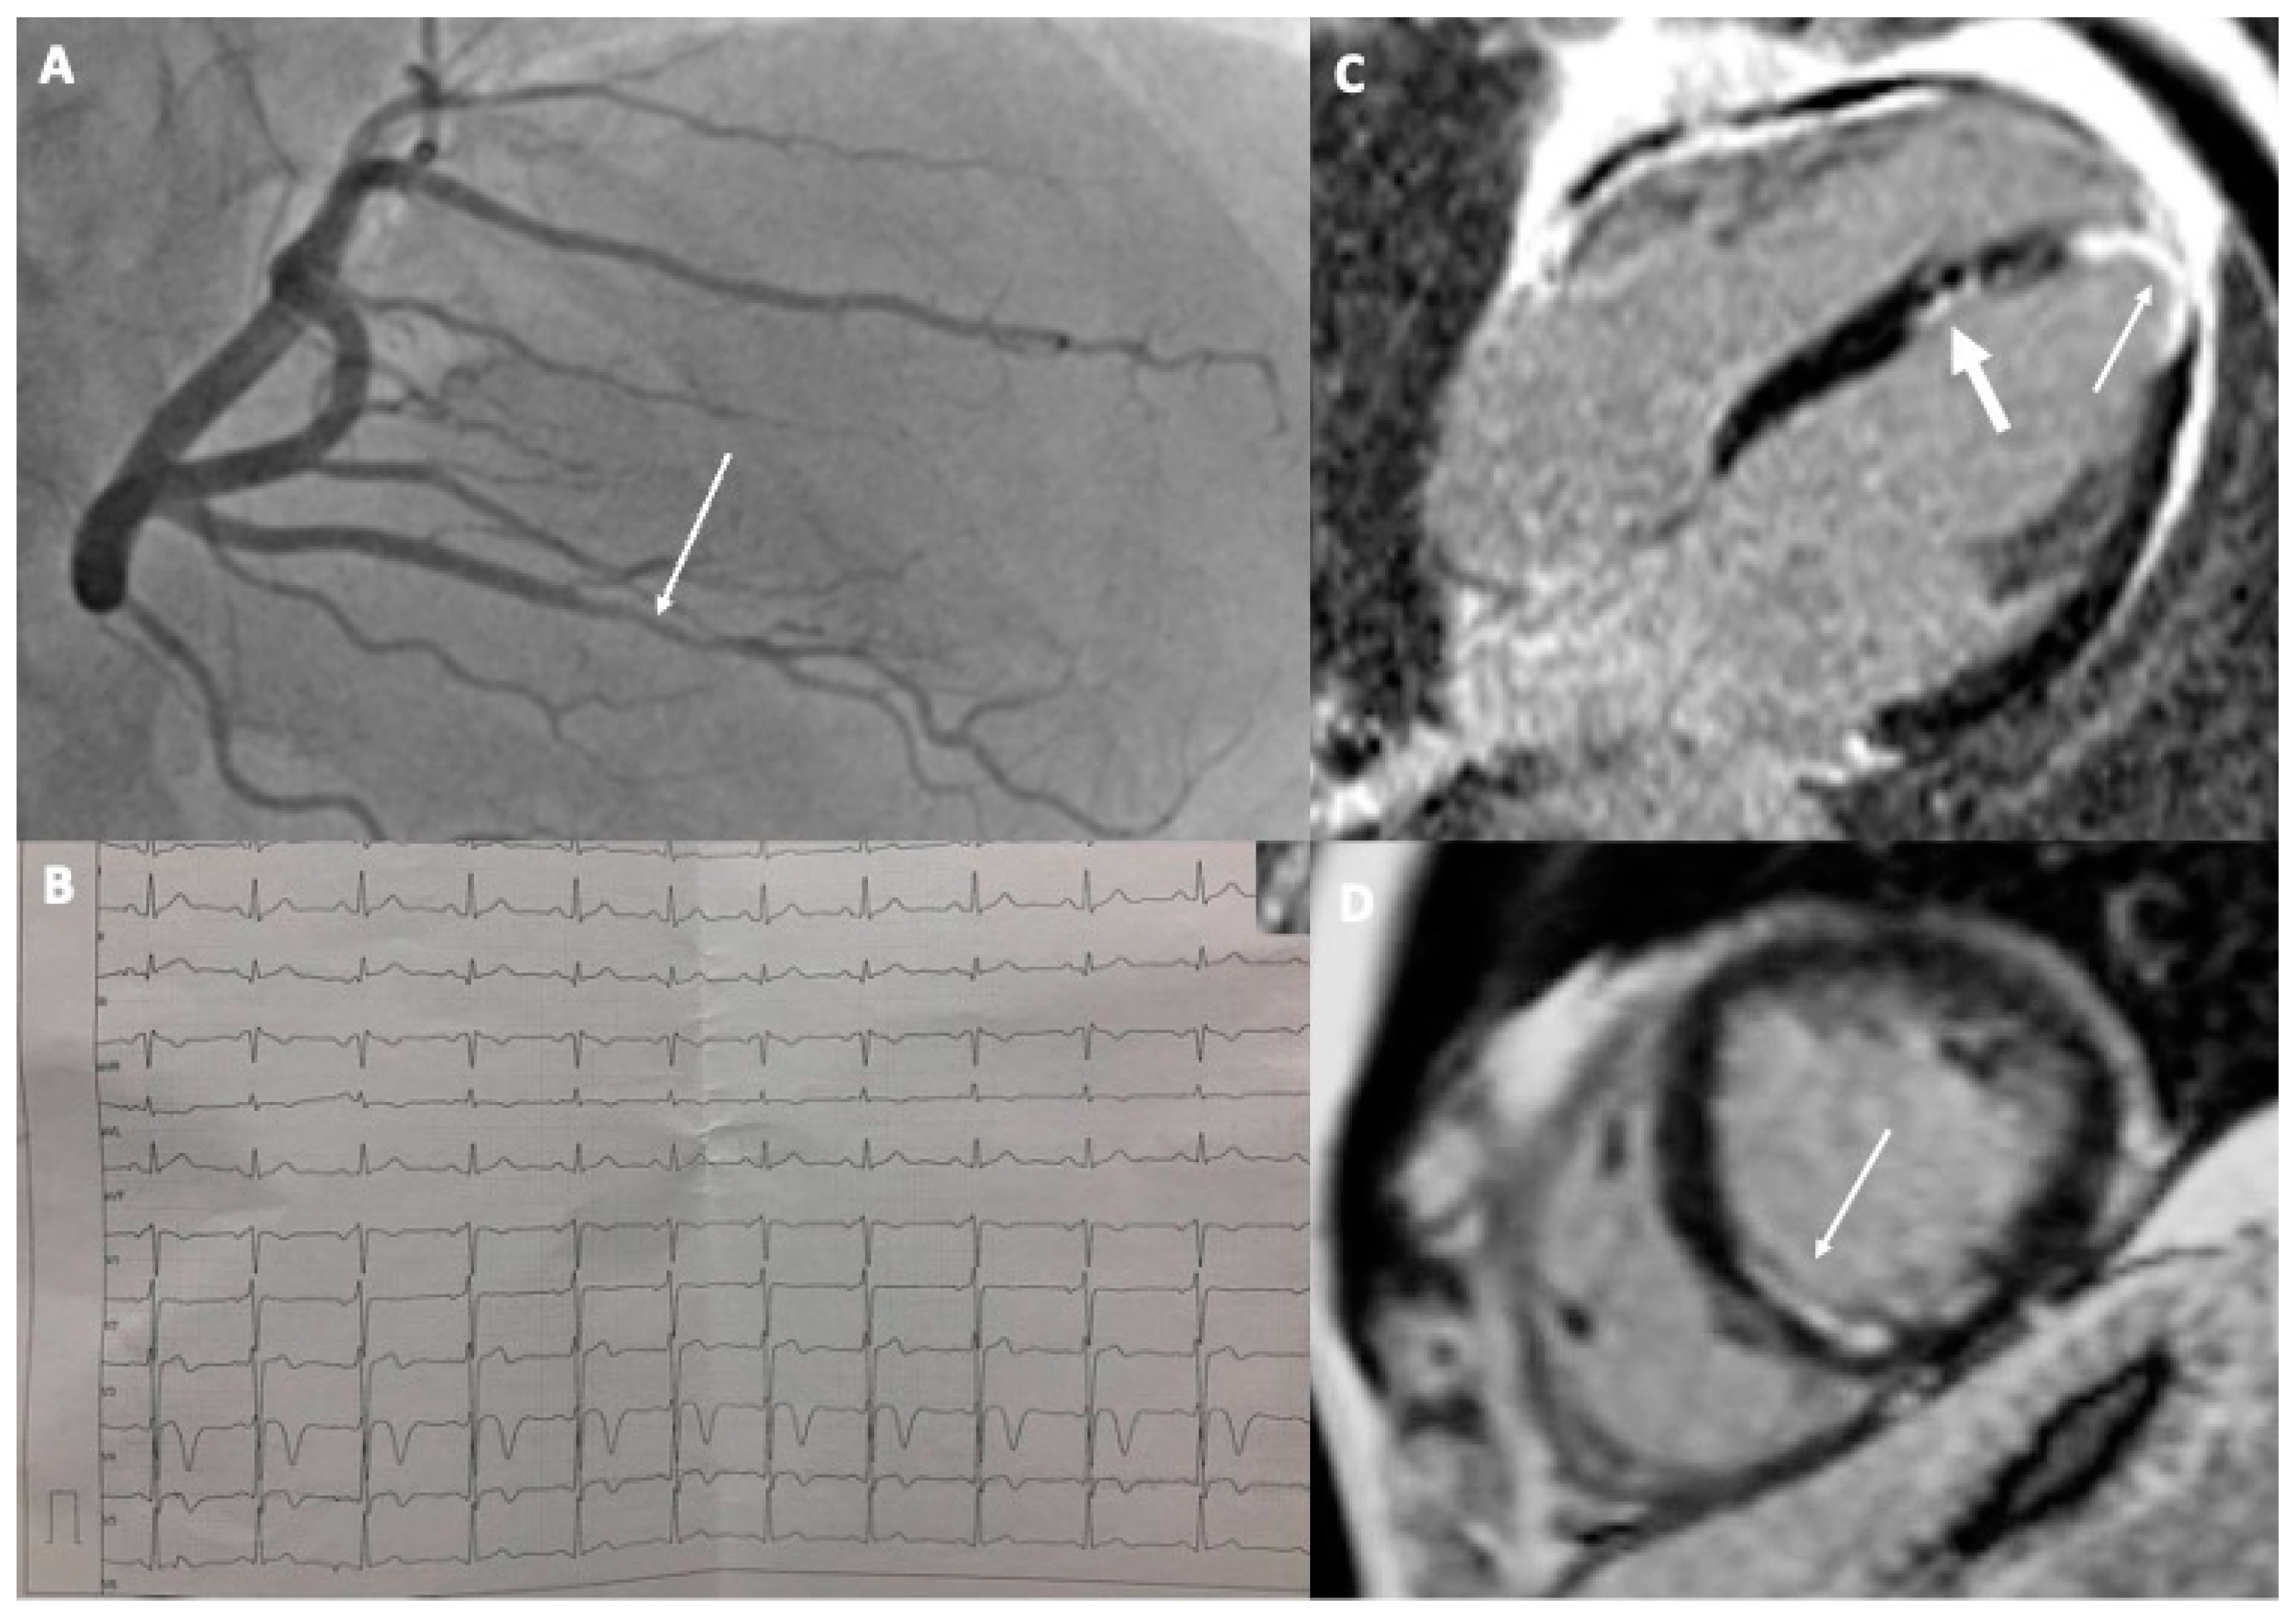

2.1. Case 1

2.2. Case 2